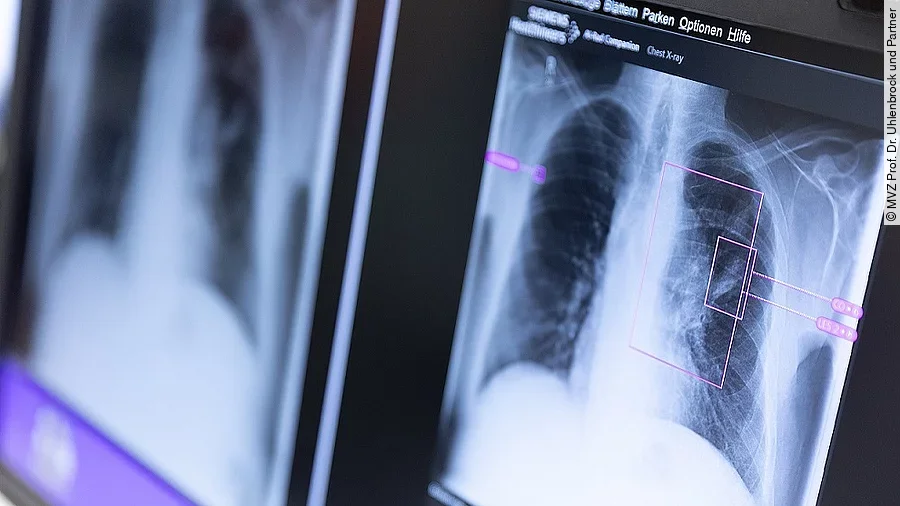

Die weltweit erste Lungendiagnostik mit KI-Unterstützung wird beim MVZ Prof. Dr. Uhlenbrock und Partner in Dortmund ausgeführt. Sie bietet neben Fehlerminimierung auch mehr Sicherheit für den Arzt und ermöglicht die Erkennung von Covid-19-Fällen. Mit dem „AI-Rad Companion Chest X-ray“ von Siemens Healthineers ist es möglich, routinemäßig Röntgenaufnahme der Lunge computergestützt auswerten zu lassen. Dabei sendet der befundende Arzt mit wenigen Klicks oder komplett automatisiert eine anonymisierte Röntgenaufnahme der Lunge an das Programm. Innerhalb weniger Minuten erhält er vom System eine Rückmeldung über mögliche Auffälligkeiten im Bild. Dabei erkennt das System die fünf häufigsten Pathologien, die zum Teil ein sofortiges Eingreifen erforderlich machen.

Die Software kann nicht nur verschiedene anatomische Strukturen voneinander unterscheiden, sondern vor allem pathologische Auffälligkeiten automatisch kennzeichnen und einordnen. Bei jedem „Treffer“ gibt das System zudem auf einer Skala von 1 bis 10 an, wie sicher es sich ist. Durch ein aktuelles Covid-Zusatzmodul ist die Software nun auch in der Lage, typische krankhafte Veränderungen zu erkennen, die durch eine Covid-19-Erkrankung verursacht worden sind. Das soll helfen, die Versorgung der Erkrankung zu beschleunigen und zu verbessern. Dieses Modul ist bisher als Prototyp verfügbar.